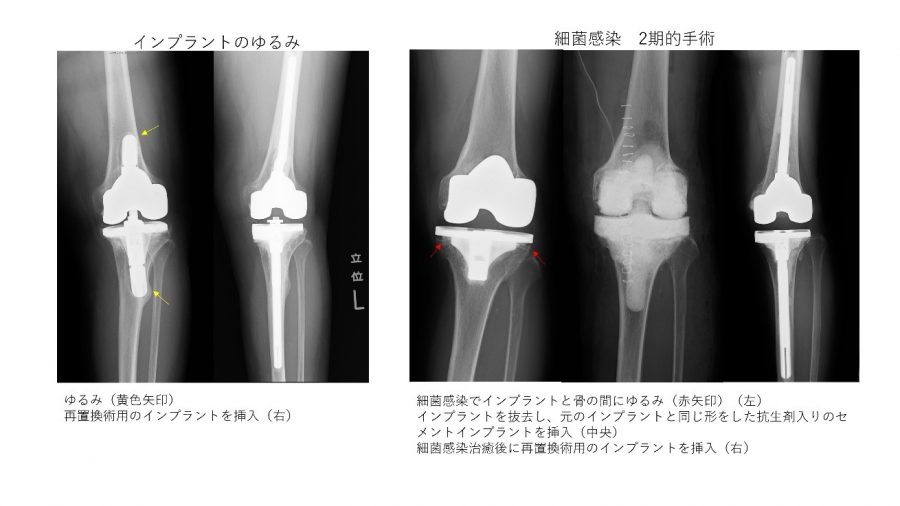

各プログラムには独自の要件と申請プロセスがあります。 OAの重症度を示す医療記録または医療画像のコピーを必要とする場合もあります。